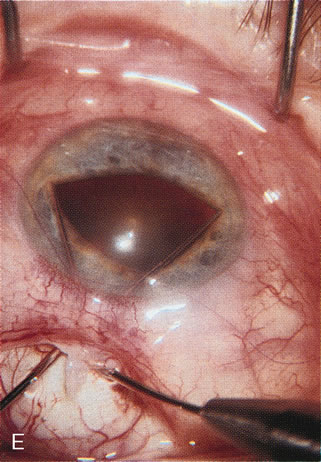

CATARACT EXTRACTION ALONE REDUCES IOP IN MOST EYES WITH ANGLE-CLOSURE GLAUCOMA

Uncomplicated cataract extraction substantially reduces IOP, along with the number of postoperative glaucoma medications in eyes with angle-closure glaucoma.146,147 When preoperative gonioscopy reveals PAS, along with adjacent areas of appositional closure, lens extraction alone in select cases may be a reasonable alternative to filtration surgery.148,149 Phacomorphic angle-closure disease due to enlargement of the lens with progressive angle crowding is eliminated following lens extraction. The width and depth of the anterior chamber angle in eyes with angle-closure glaucoma increases significantly after cataract extraction with IOL implantation and becomes similar to open-angle glaucoma and normal eyes.150,151 (Fig. 5). Combining phacoemulsification, IOL implantation, and limited goniosynechialysis is effective in the treatment of cataract and chronic angle-closure glaucoma.152 Phacoemulsification with implantation of a foldable IOL is more effective in reducing IOP and improving visual acuity than surgical peripheral iridectomy in eyes with acute angle-closure glaucoma.153

Fig. 5. Anterior chamber angle changes associated with lens extraction and PCIOL This 65-year-old Vietnamese woman has a long-standing history of chronic angle-closure glaucoma treated with laser peripheral iridectomy. The optic nerve demonstrated mild glaucomatous damage and IOP was moderately controlled on two antiglaucoma medications. The cataract was removed through temporal clear corneal phacoemulsification with foldable acrylic IOL. A. Symptomatic cataract in narrow-angle glaucoma eye with patent iridectomy. B. Intraoperative goniophotograph showing crowding of angle with increasing narrowness due to phacomorphic component. C. Intraoperative photograph showing temporal clear corneal approach with IOL in the capsular bag. D. Intraoperative goniophotograph demonstrating deepening of chamber angle following lens extraction. Proposed theories for IOP reduction following lens extraction with complete wound closure:

1. Anterior chamber deepening with improved access to trabecular meshwork

2. Increase in traction on the trabecular meshwork

3. Improved outflow facility mediated by an increase in prostaglandin release

4. Reduction in aqueous humor production

5. Atrophy of ciliary body processes

6. Goniosynechialysis due to intraoperative over deepening of AC with viscoelastic

7. Relief of undiagnosed pupil block